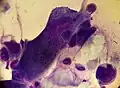

![]() A positive Tzanck test, showing three multinucleated giant cells ("Tzanck cells") in center. | |

Herpetic infections | Acantholytic cells, multinucleated giant cells and eosinophilic inclusion bodies | 53.1 - 86% sensitive and 100% specific | ||